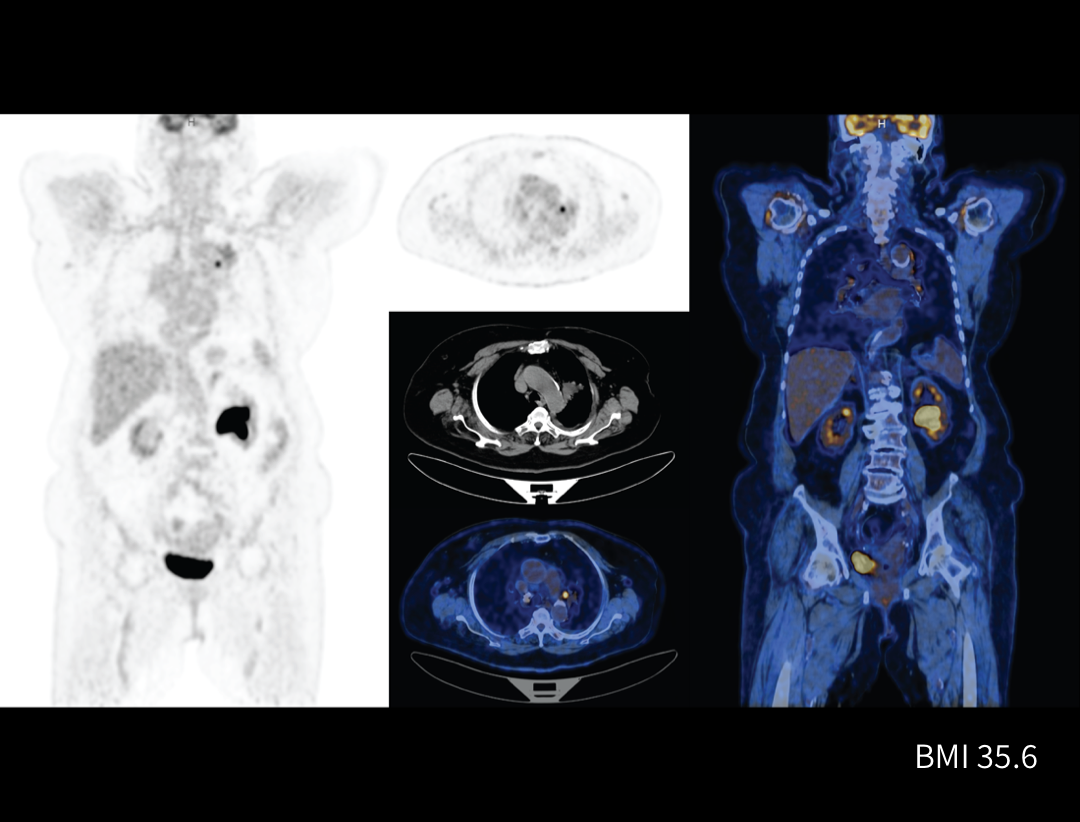

Integrated Oncology Application

The uMI 550 offers a comprehensive solution package for tumor diagnosis and post-therapeutic evaluation on the operation console.